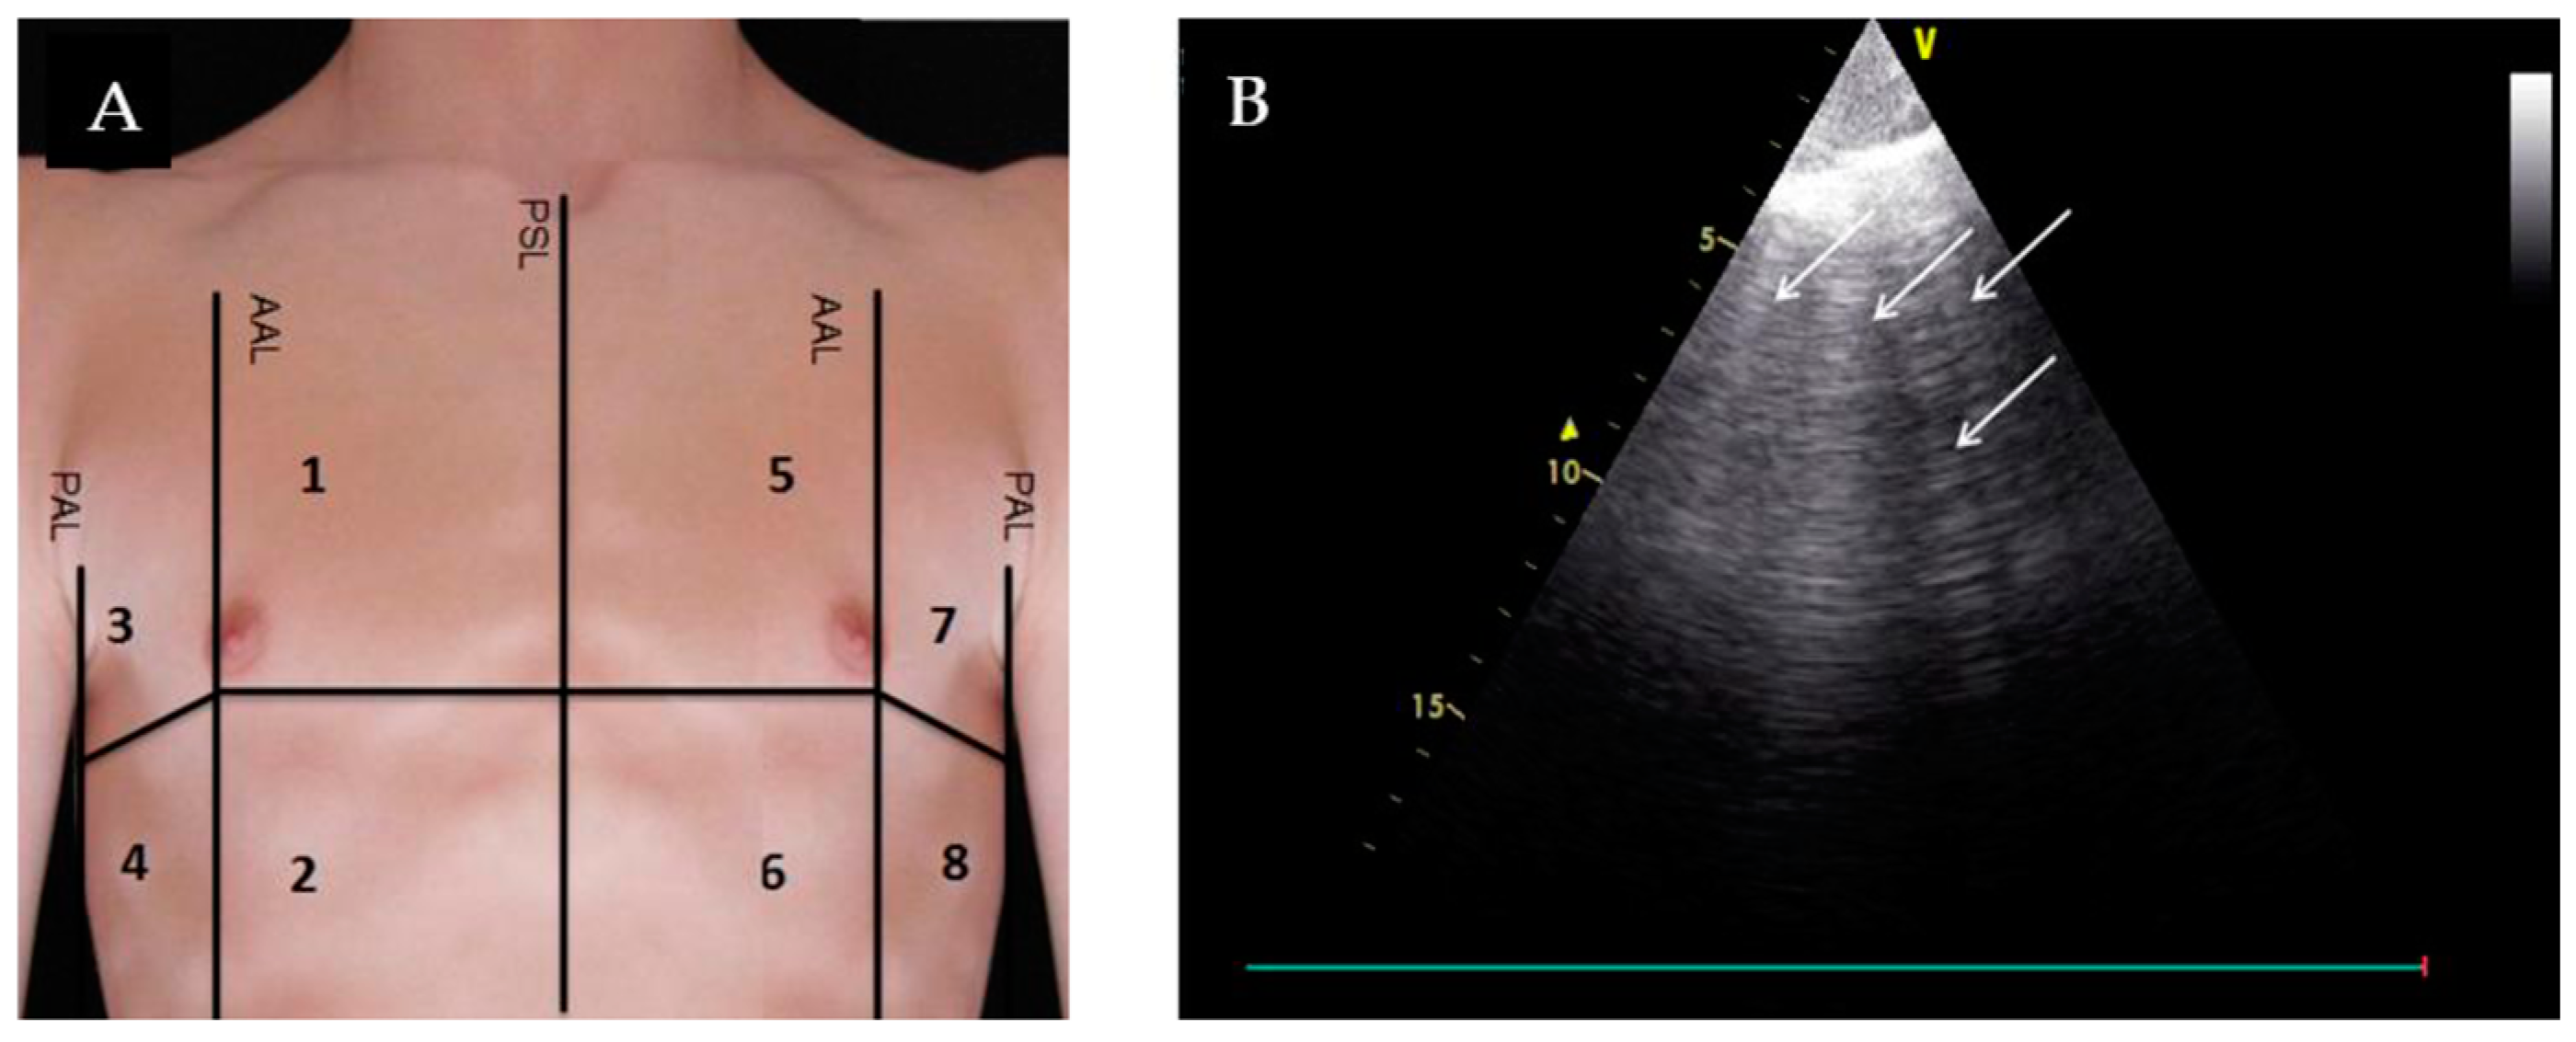

- Glockner, E.; Wening, F.; Christ, M.; Dechene, A.; Singler, K. Lung Ultrasound Eight-Point Method in Diagnosing Acute Heart Failure in Emergency Patients with Acute Dyspnea: Diagnostic Accuracy and 72 h Monitoring. Medicina 2020, 56, 379. [Google Scholar] [CrossRef] [PubMed]